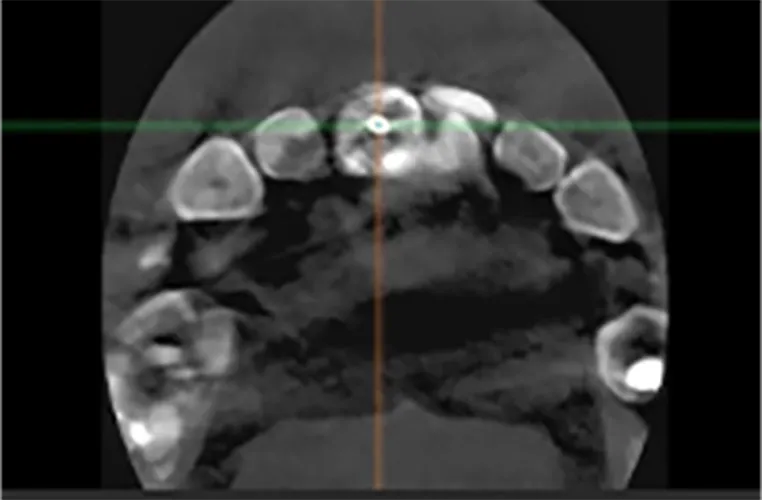

骨の中に神経•血管に損傷のないように

完全安心で確実な手術が実践できる

インプラントの手術では、あごの骨の中にある神経や血管をしっかりと避けることがとても大切です。サージカルガイドを用いて安全・正確な手術を行っています。

安全な手術を確実にする理由

手術の計画・実行を

精緻にできる

治療計画

神経や血管の位置を

CTで正確に把握

あらかじめ「ここに神経がある」という情報をもとに、安全な位置だけを選びます。